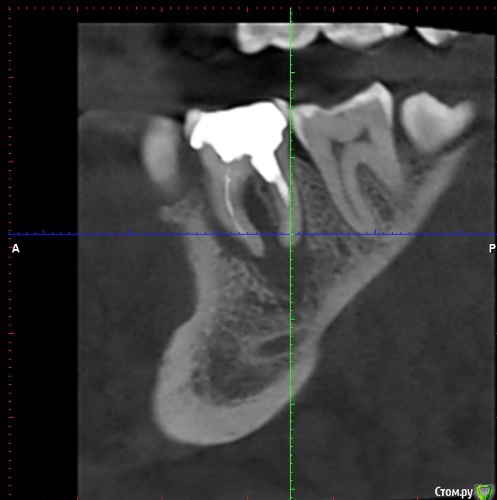

Constantine Опубликовано 30 января, 2019 Автор Поделиться Опубликовано 30 января, 2019 (изменено) Здравствуйте, На первый вопрос не отвечу , не эксперт, давать подобные заключения не могу - форум в принципе ориентирован на помощь в решении клинических вопросов . По поводу 2 го вопроса , скорее всего удаление ( скиньте срезы КТ , а не 3D виртуальную модель 36го зуба) .Вот это? Изменено 30 января, 2019 пользователем Constantine Ссылка на комментарий

___49___ Опубликовано 30 января, 2019 Поделиться Опубликовано 30 января, 2019 Вот это?да - удаляйте зуб. 3 Ссылка на комментарий